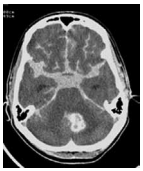

O que indica o sinal do Delta vazio?

TROMBOSE VENOSA CENTRAL